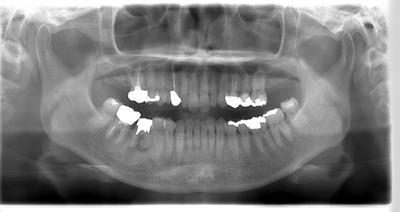

初診時のパノラマレントゲン

説明:

初診時のパノラマレントゲンです。右上の歯が虫歯によって大きく欠けているのがわかります。